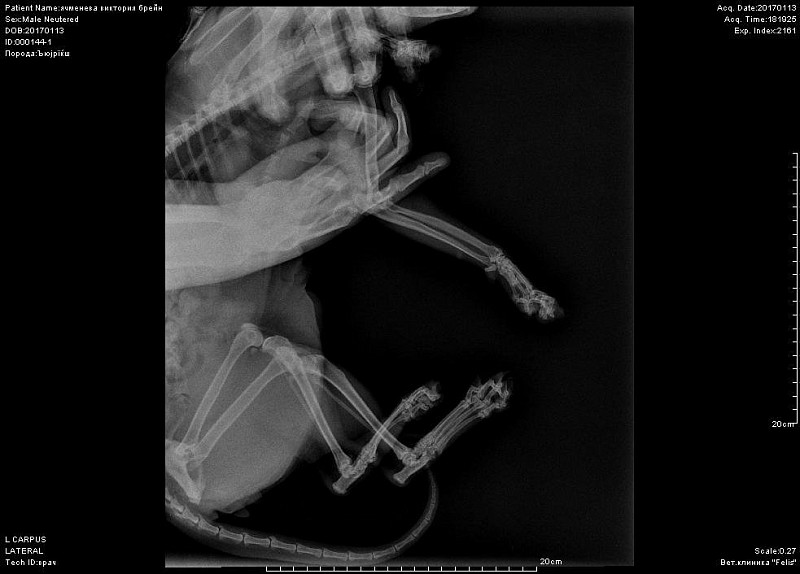

Периодически хромает после долгого лежания.Около 10 дней хромота не прошла, стал не наступать на переднюю лапу-ходит на трех. Повели в к врачу, при осмотре спокоен. Сделали снимок-врач сказал, что был когда-то компрессионный перелом лучевой кости, сказал, что кот хоить нормально больше не будет. Нужно еще мнение, посмотрите снимок, пожалуйста.

Добрый день! не вижу перелома на этом снимке. Нужна еще прямая проекция. Боль именно в запястном суставе?

К сожалению не знаем, где болит-реакции на пальпацию и энергичные движения в суставах не выявили. Именно на этом снимке врач мне указал на компрессию кости-как он сказал кость посередине должна быть квадратная, а она стала треугольной... Я сама нашла атлас посмотрела, что это нормальный вид лучевой кости.

вот такой снимок целиком-первое фото-это я увеличила, может быть другие суставы на этой лапе Вы тоже посмотрите. А также, пожалуйста, порекомендуйте кому можно показать кота в спб, может Вы знаете.

вот в запястном суставе не вижу изменений.А вот локтевом есть признаки артроза. Но все же это не прямая и даже не боковая проекция локтя.